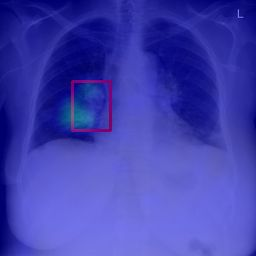

Deployments of artificial intelligence in medical diagnostics mandate not just accuracy and efficacy but also trust, emphasizing the need for explainability in machine decisions. The recent trend in automated medical image diagnostics leans towards the deployment of Transformer-based architectures, credited to their impressive capabilities. Since the self-attention feature of transformers contributes towards identifying crucial regions during the classification process, they enhance the trustability of the methods. However, the complex intricacies of these attention mechanisms may fall short of effectively pinpointing the regions of interest directly influencing AI decisions. Our research endeavors to innovate a unique attention block that underscores the correlation between 'regions' rather than 'pixels'. To address this challenge, we introduce an innovative system grounded in prototype learning, featuring an advanced self-attention mechanism that goes beyond conventional ad-hoc visual explanation techniques by offering comprehensible visual insights. A combined quantitative and qualitative methodological approach was used to demonstrate the effectiveness of the proposed method on the large-scale NIH chest X-ray dataset. Experimental results showed that our proposed method offers a promising direction for explainability, which can lead to the development of more trustable systems, which can facilitate easier and rapid adoption of such technology into routine clinics. The code is available at www.github.com/NUBagcilab/r2r_proto.